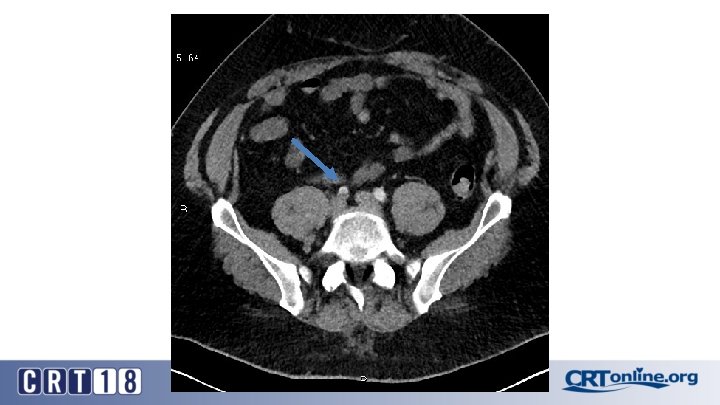

Blue Toe Syndrome

Returns Next day

Failed recanalization: BKA